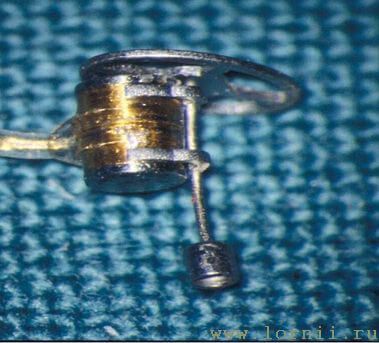

Функция системы Vibrant Sоundbridge заключается в трансформации звуков непосредственно в колебания цепи слуховых косточек среднего уха или в колебания жидкости улитки (перилимфы). Система состоит из двух частей: внутренней – имплантируемой, импланта (Vibration Ossicular Prosthesis, VORP) и наружной – аудиопроцессора (Audio Processor, AP).

Имплантируемая внутренняя часть состоит из постоянного магнита, катушки, принимающей электромагнитные сигналы, соединительного кабеля и устройства, приводящего в движение слуховые косточки или жидкость улитки – Floating Mass Transducer (FMT).

Аудиопроцессор содержит микрофон, элемент питания и электронику. Он располагается снаружи, скрыт волосами и удерживается с помощью магнита (рис. 4, 5).